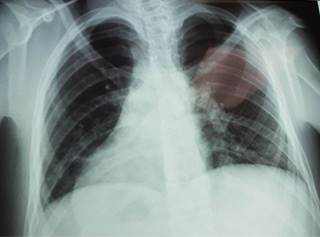

Se realizó la apendicectomía con técnica de Halsted y drenaje de absceso y no hubo incidentes. Durante el postoperatorio inmediato se solicitó una radiografía de tórax (Figura 3), la cual mostró dextrocardia, y el ultrasonido abdominal reportó transposición de las vísceras abdominales, confirmando el diagnóstico de situs inversus totalis. Al tercer día postoperatorio, el paciente presentó mejoría clínica y, al no presentar datos de complicaciones postoperatorias, se decide su egreso.